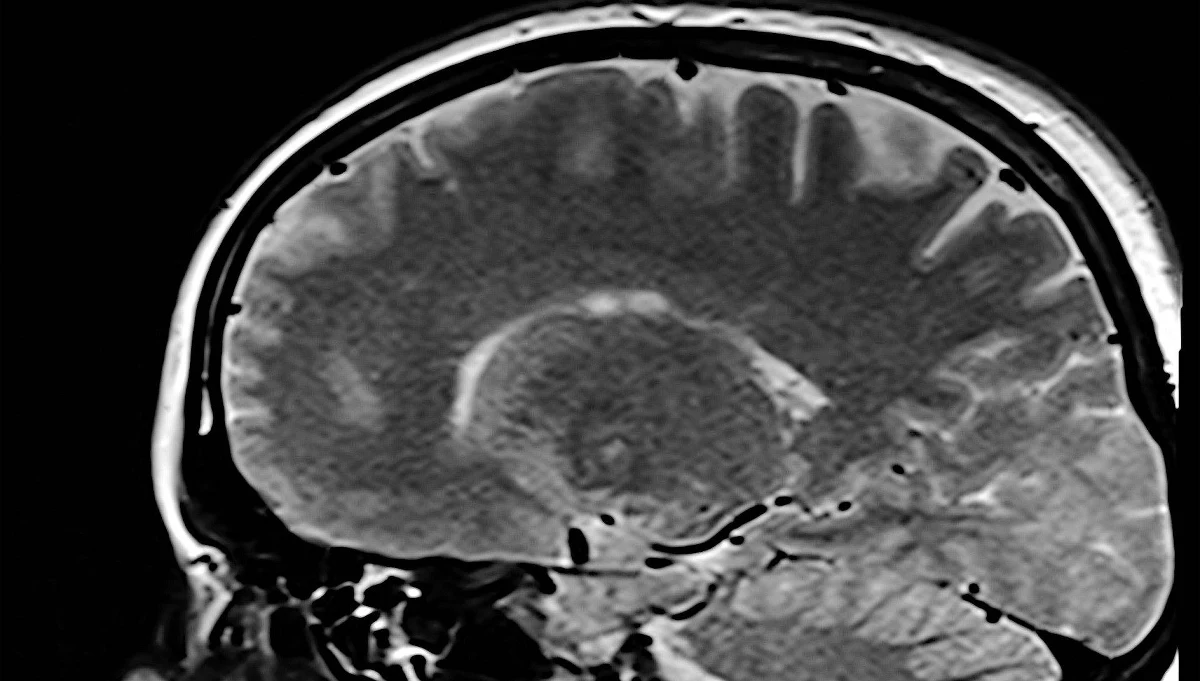

Ważne odkrycie francuskich i amerykańskich naukowców w walce z chorobą Alzheimera. Twierdzą oni, że znaleźli sposób na spowolnienie rozwoju tej choroby poprzez dążenie do lepszego ukrwienia mózgu.

Naukowcy z Uniwersytetu w Tuluzie i z amerykańskiego Uniwersytetu Cornella stwierdzili, ze rozwój choroby Alzheimera przyspiesza - szczególnie w pierwszej fazie - słabe ukrwienie mózgu. Opracowali więc terapie umożliwiającą lepszy dopływ krwi do mózgu.

Testy przeprowadzone na myszach zakończyły się sukcesem. Symulacje komputerowe sugerują, że terapia ta może spowolnić rozwój choroby Alzheimera u człowieka. Zanim jednak zostanie ona rozpowszechniona, trzeba będzie m.in. przeprowadzić testy kliniczne z udziałem ochotników, które potwierdza jej skuteczność w przypadku ludzkiego organizmu.